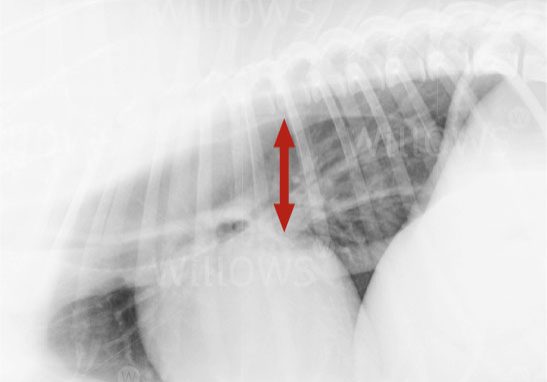

Megaoesophagus is diagnosed by taking x-rays of the chest. As sedative drugs or general anaesthesia can cause gas to build up in the oesophagus and mimic the appearance of a megaoesophagus, it is important that the x-rays are obtained without sedation or anaesthesia. Blood tests are performed to look for secondary causes (found in 30-40% of cases).

Image 1: Chest x-ray of a dog showing megaoesophagus (the arrow indicates the diameter of the oesophagus)